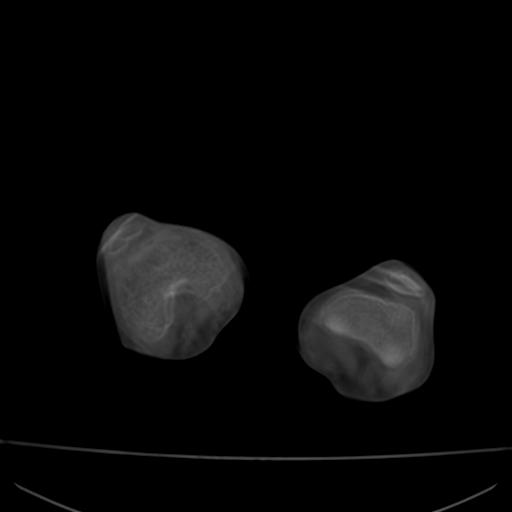

标题: PED0940:M12Y,左股骨下端酸痛畸形 [打印本页]

标题: PED0940:M12Y,左股骨下端酸痛畸形

12岁男孩,左膝关节肿痛8年,近月明显